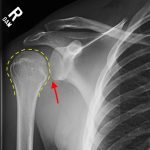

Radiographs demonstrated posterior displacement of the humeral head on the “Y” view (see white arrow) and widening of the glenohumeral joint space on anterior-posterior view (see red arrow). The findings were consistent with posterior dislocation and a Hill-Sachs type deformity.  Sedation was performed and reduction was attempted using external rotation, traction counter-traction. An immediate “pop” was felt during the procedure. Post-procedure radiographs revealed a persistent posterior subluxation with interlocking at posterior glenoid. CT revealed posterior dislocation with acute depressed impaction deformity medial to the biceps groove with the humeral head perched on the posterior glenoid, interlocked at reverse Hill-Sachs deformity (see blue arrow).